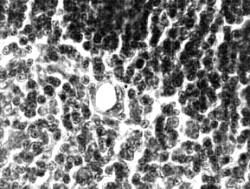

пустая полость (рис.1). В опыте-1 через

30 сут после имплантации облученной лазером аллогенной мышечной ткани

количество мозгового вещества в тимусе имело тенденцию к увеличению

(19.00±1.53%). На фоне достоверного повышения МИ тимоцитов (14.69‰±1.08, p<0.01) число клеток с

пикнотическими ядрами не превышало уровень в контроле-1 (0.44±0.09%).

Количество телец Гассаля увеличивалось до 1.9 на ед. площади. Кроме телец с

образующейся полостью встречались тельца, в полости которых видны клетки с

распадающимися ядрами (рис. 2). Контроль-2. Предварительное воздействие